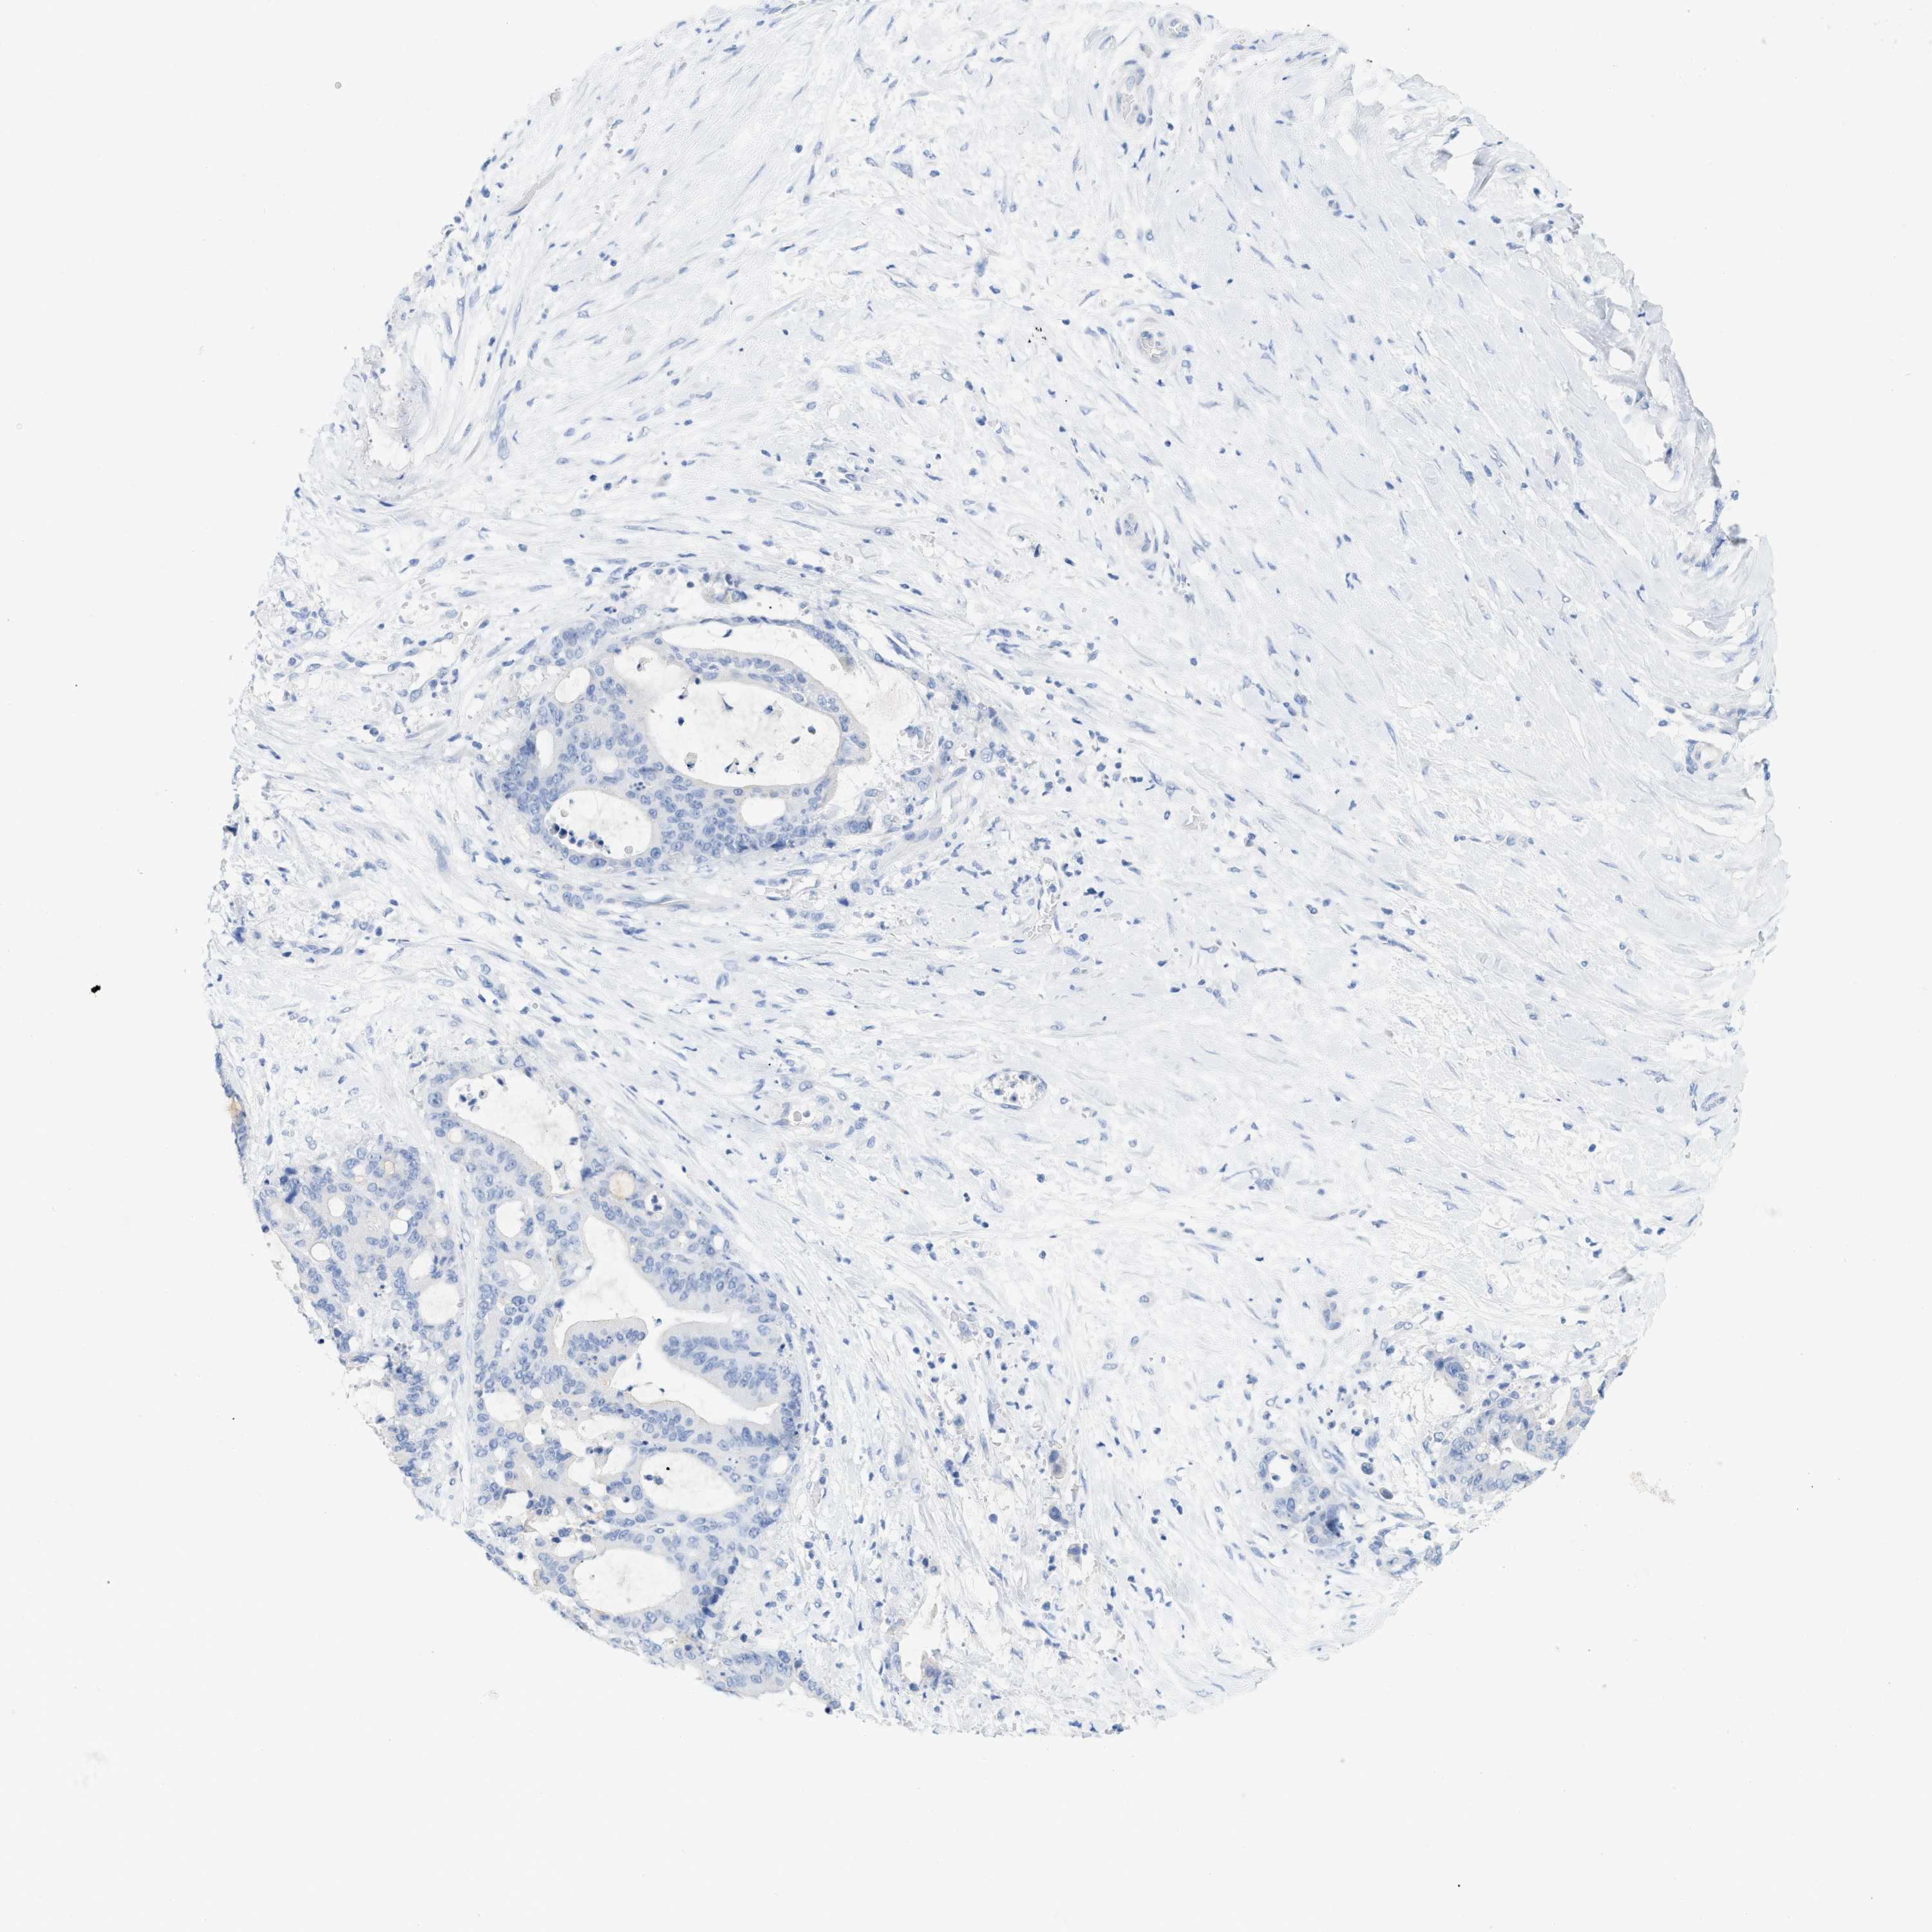

LIVER CANCER - Protein expressioni

A mouse-over function shows sample information and annotation data. Click on an image to view it in a full screen mode. Samples can be filtered based on level of antibody staining by selecting one or several of the following categories: high, medium, low and not detected. The assay and annotation is described here.

Note that samples used for immunohistochemistry by the Human Protein Atlas do not correspond to samples in the TCGA dataset.

Antibody stainingi

Antibody staining in the annotated cell types in the current human tissue is reported as not detected, low, medium, or high, based on conventional immunohistochemistry profiling in selected tissues. This score is based on the combination of the staining intensity and fraction of stained cells.

Each image is clickable and will lead to virtual microscopy that enables deeper exploration of all samples and also displays staining intensity scores, fraction scores and subcellular localization as well as patient and tissue information for each sample.

Antibody HPA001667

Antibody CAB016724

Staining

High

Medium

Low

Not detected

Intensity

Strong

Moderate

Weak

Negative

Quantity

>75%

75%-25%

<25%

None

Location

Nuclear

Cytoplasmic/membranous

Cytoplasmic/membranous,nuclear

Cholangiocarcinoma

Carcinoma, Hepatocellular, NOS